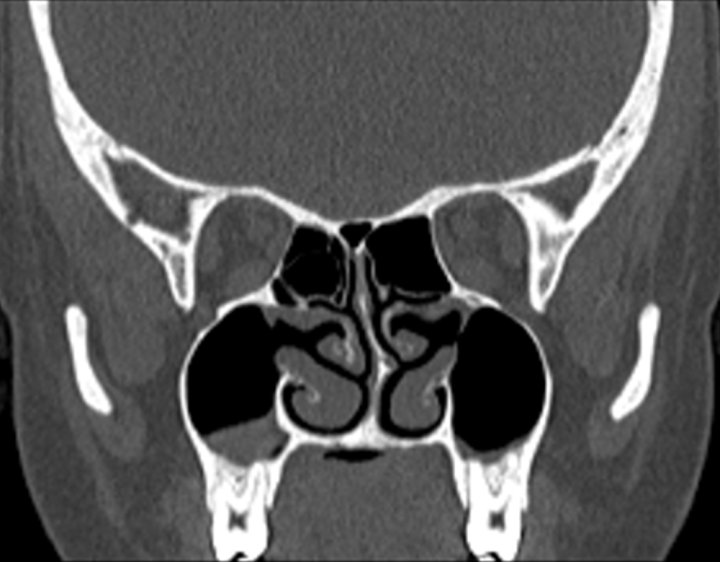

002